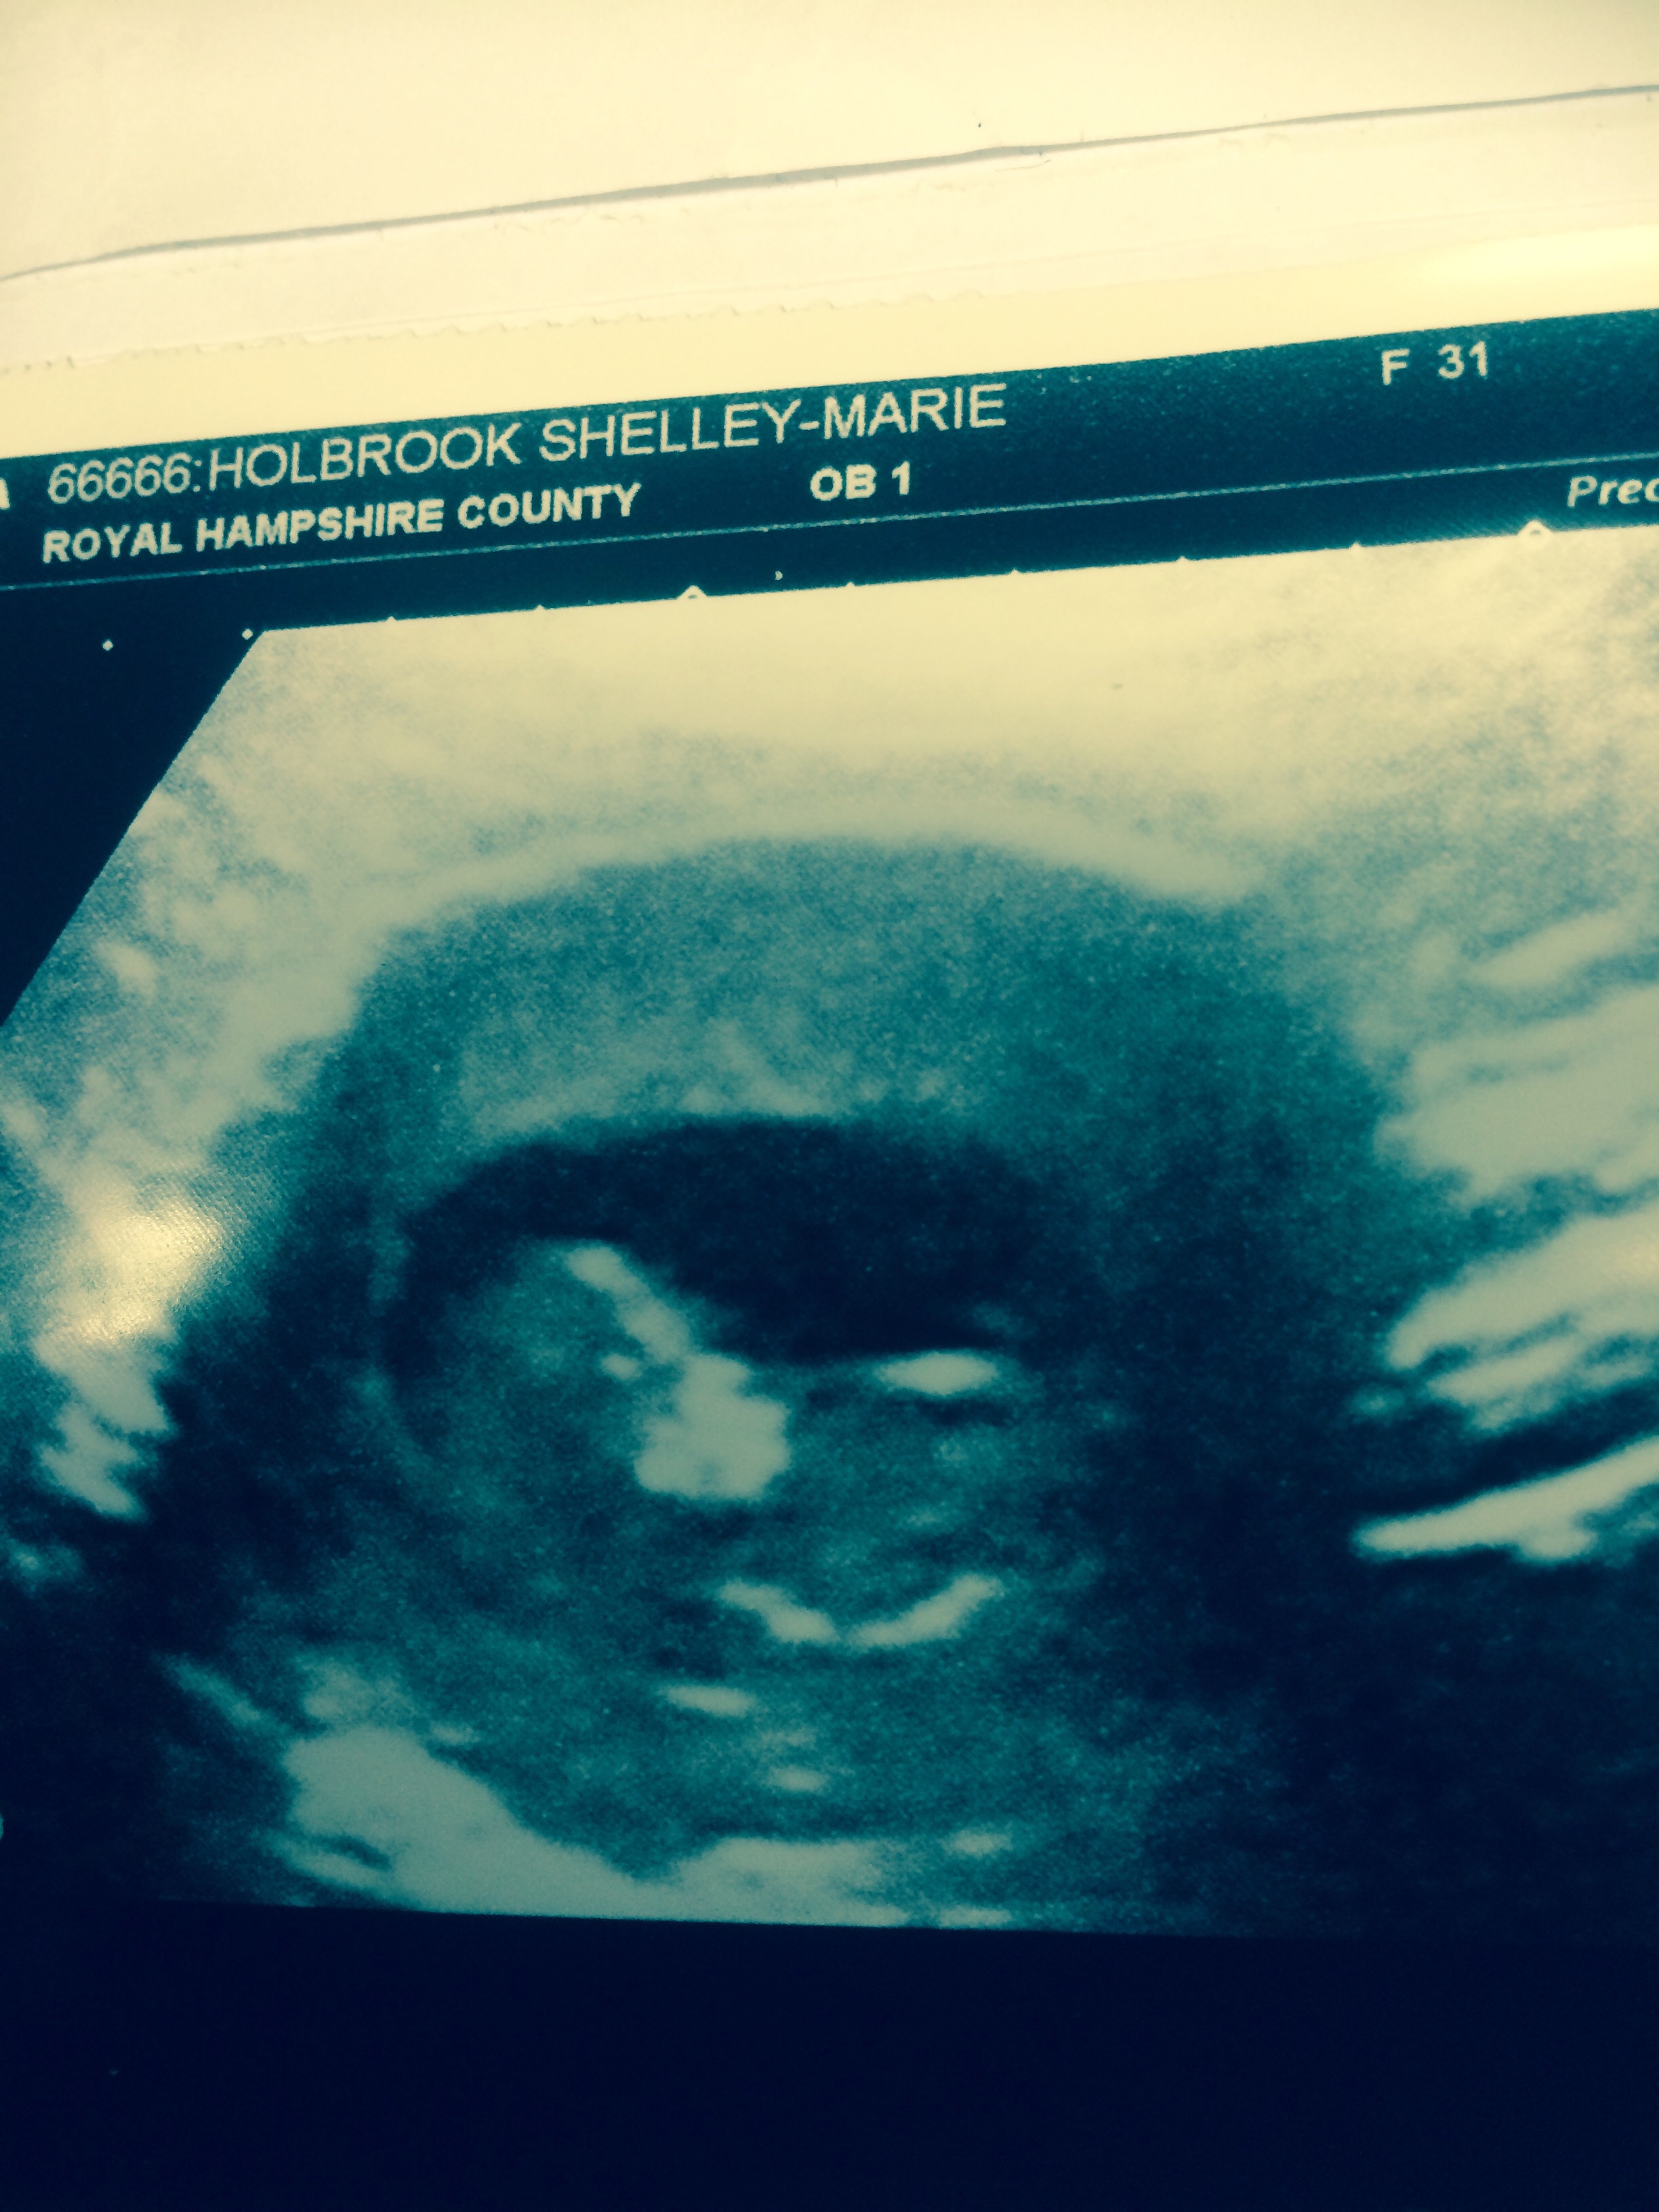

Had my NT ultrasound yesterday and everything looked great! Moving and flipping around! I'm 12 weeks 4 days according to the NT ultrasound, a couple days ahead of what I thought! So amazing!!!